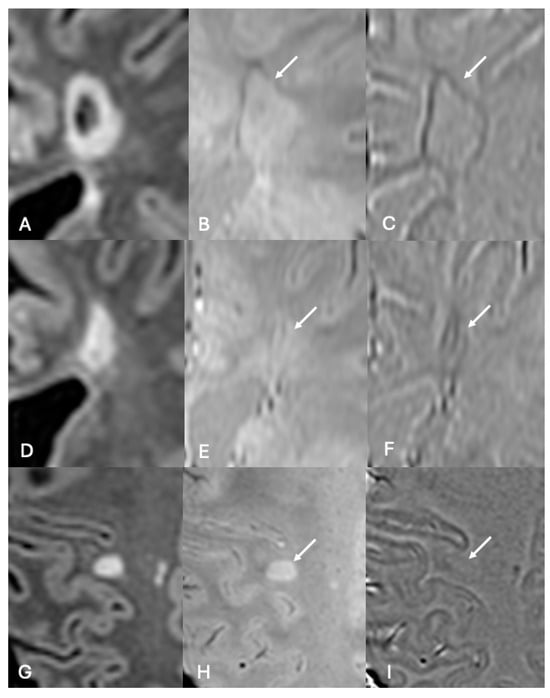

3.2. Paramagnetic Rim Lesions